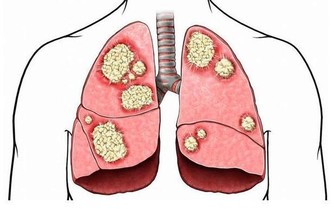

*****1.切記吃太鹹,易引發胃癌*****

食鹽過多不僅會引發高血壓、氣管炎,還可增加胃癌的發病風險。高鹽膳食使胃酸減少,抑制前列腺素E2,使胃黏膜易受損,發生胃炎或胃潰瘍,繼而引發胃癌。喜食醃製食品也是誘發胃癌的一大因素。因為醃製的菜會產生亞硝酸鹽,亞硝酸鹽在胃中與胺類物質結合形成的亞硝胺可引發胃癌。